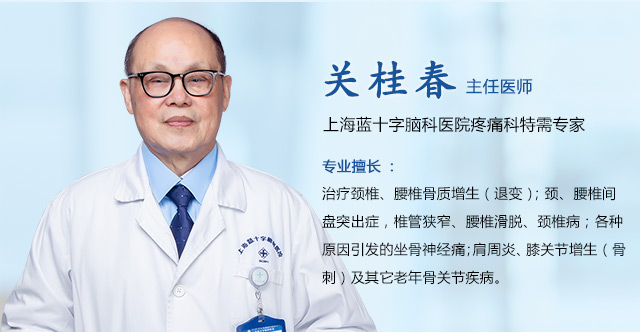

患者崔先生(化名)3天前无诱因突然出现失明、头痛等症状,在当地医院行头颅CT后疑似脑梗,未能明确。随后,为明确诊断治疗,慕名到上海蓝十字脑科医院就诊。

经检查,患者GCS评分15分,神志清,对答切题,双眼失明,光感消失,双侧瞳孔等大等圆,直径约3.5mm对光反应均消失。

针对患者情况,6B病区主任潘仁龙基于多年临床经验立即作出判断,急行头颅鞍区MRI平扫+增强,显示:蝶鞍扩大,鞍底骨质下陷;鞍内垂体上缘膨隆,腺垂体中央见一枚类椭圆形异常信号,大小约2.8*1.9cm;T1WI上呈等信号、T2WI呈等信号为主局部见斑片状低信号,轮廓光整,增强后可见大部分明显强化,视交叉可见上抬。考虑为垂体腺瘤伴局部卒中。

潘仁龙主任指出,CT在垂体卒中急性期平扫时即可见瘤内的高密度影出血灶,很容易辨别,但当进入亚急性期后则呈等密度,难于鉴别。因此,在高度怀疑垂体卒中的病例中应首选MRI扫描。此外,MRI 还能提供较 CT 更为清晰的三维空间解剖结构,它对肿瘤以及瘤体与周边正常组织的关系都可起到良好的显示作用。因此MRI是垂体瘤卒中的首选影像学检查手段,而在急性期,尤其是超急性期则首选CT。

▲ 李士其教授正在为患者手术

彼时患者已经出现失明情况,手术指征明确,情况紧急,应立即进行手术。

在充分准备并征得家属同意后,李士其教授在吴治群博士、黄秀夫医生协助下为患者行经蝶窦入路垂体瘤切除术,经右侧鼻腔蝶窦入路将肿瘤切除。

术后第二天,患者双眼已经有明显光感,目前正在康复中。

李士其教授指出,垂体腺瘤出现垂体卒中的比例为1%-2%,但症状不明显的亚临床出血约占所有垂体瘤的10%左右。不少垂体卒中患者缺乏原有垂体腺瘤的症状,因此遇到原因不明的突发颅压增高,尤其伴视力障碍、眼肌麻痹等压迫症状者,应警惕垂体卒中。出现严重的视力减退、视野缺损以及意识障碍或症状持续加重时,应该首选手术且尽早手术。